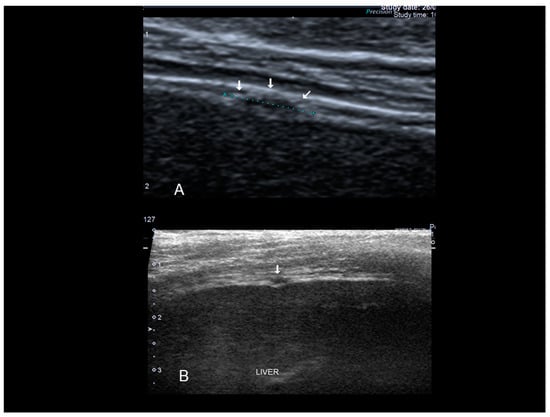

Figure 17. Hepatic superficial endometriosis (see white arrow) confirmed at surgery (A,B).

Figure 21. Diaphragmatic endometriosis (see white arrow) confirmed at surgery (A,B).

3.3. Hepatic Endometriosis

This condition is one of the rarest sites of extra-pelvic endometriosis with only 22 reported cases up to now. How the endometrial cells reach the liver is unclear although mechanisms of lymphatic spread of endometrial tissue have been hypothesized. Endometriotic lesions within the hepatic parenchyma can be visualized through ultrasound, computerized tomography (CT) and magnetic resonance imaging (MRI) albeit no pathognomonic features have been described for any of these imaging techniques, therefore a definite diagnosis is completely reliant on histopathological examination [29]. Liver endometriosis is also hard to diagnose and its appearance through imaging techniques may mimic an echinococcal cysts, an abscess, a hematoma, a cystadenoma or a malignancy such as cystadenocarcinoma, or a metastasis [26]. On the contrary superficial hepatic endometriosis is characterized by small hypoechoic lesion interrupting the hepatic capsula, usually hyperechoic (Figure 17).

3.6. Thoracic Endometriosis

Thoracic endometriosis (TE) is an endometriotic lesion that involves the diaphragm, pleura, and/or lung. Lung is rare, but diaphragm lesions are not so rare [5,7,32]. The typical manifestation of diaphragmatic endometriosis is catamenial pneumothorax. Usually the diagnosis is performed using MRI in the absence of reports regarding ultrasound findings. Diaphragmatic endometriosis is characterized by ultrasound as small hypoechoic lesion (Figure 20 and Figure 21).